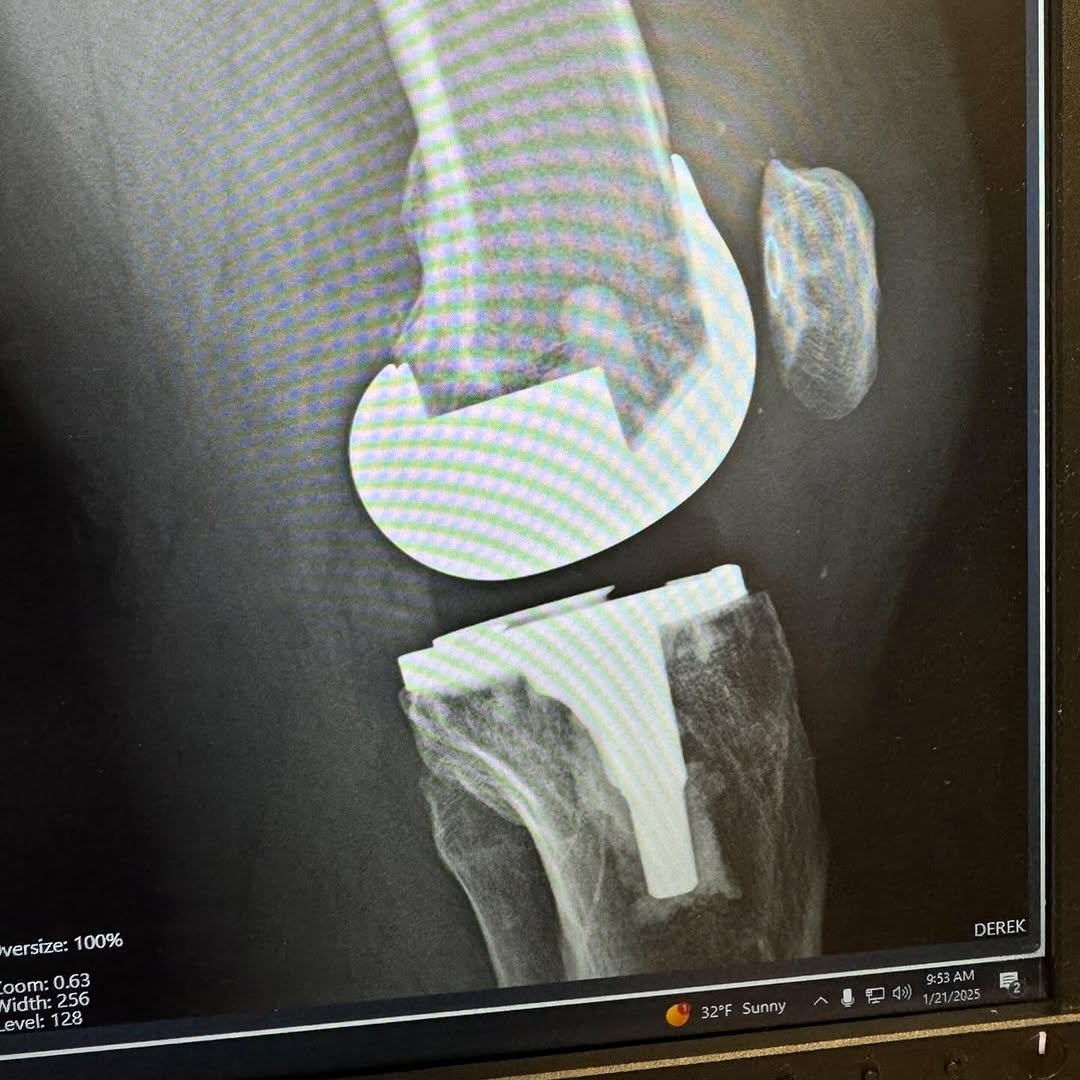

I am 7 weeks post op on a Total Knee Replacement. My left knee was on its last leg, and I have been putting this surgery off for years. Post op X-Rays show everything is healing nicely. Many thanks to Dr. Nicholas Dirig, Derek Bobst, and their excellent team for my surgery. Thanks to Bill Wall of Physical Therapy Specialist for getting me back on track.

Austin shared the following photos: